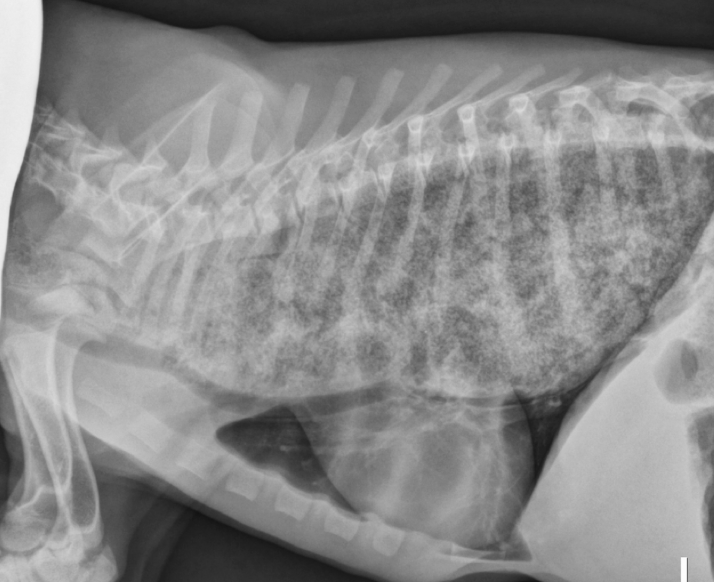

11

Esophageal dilation

Arrow = tracheal stripe

12